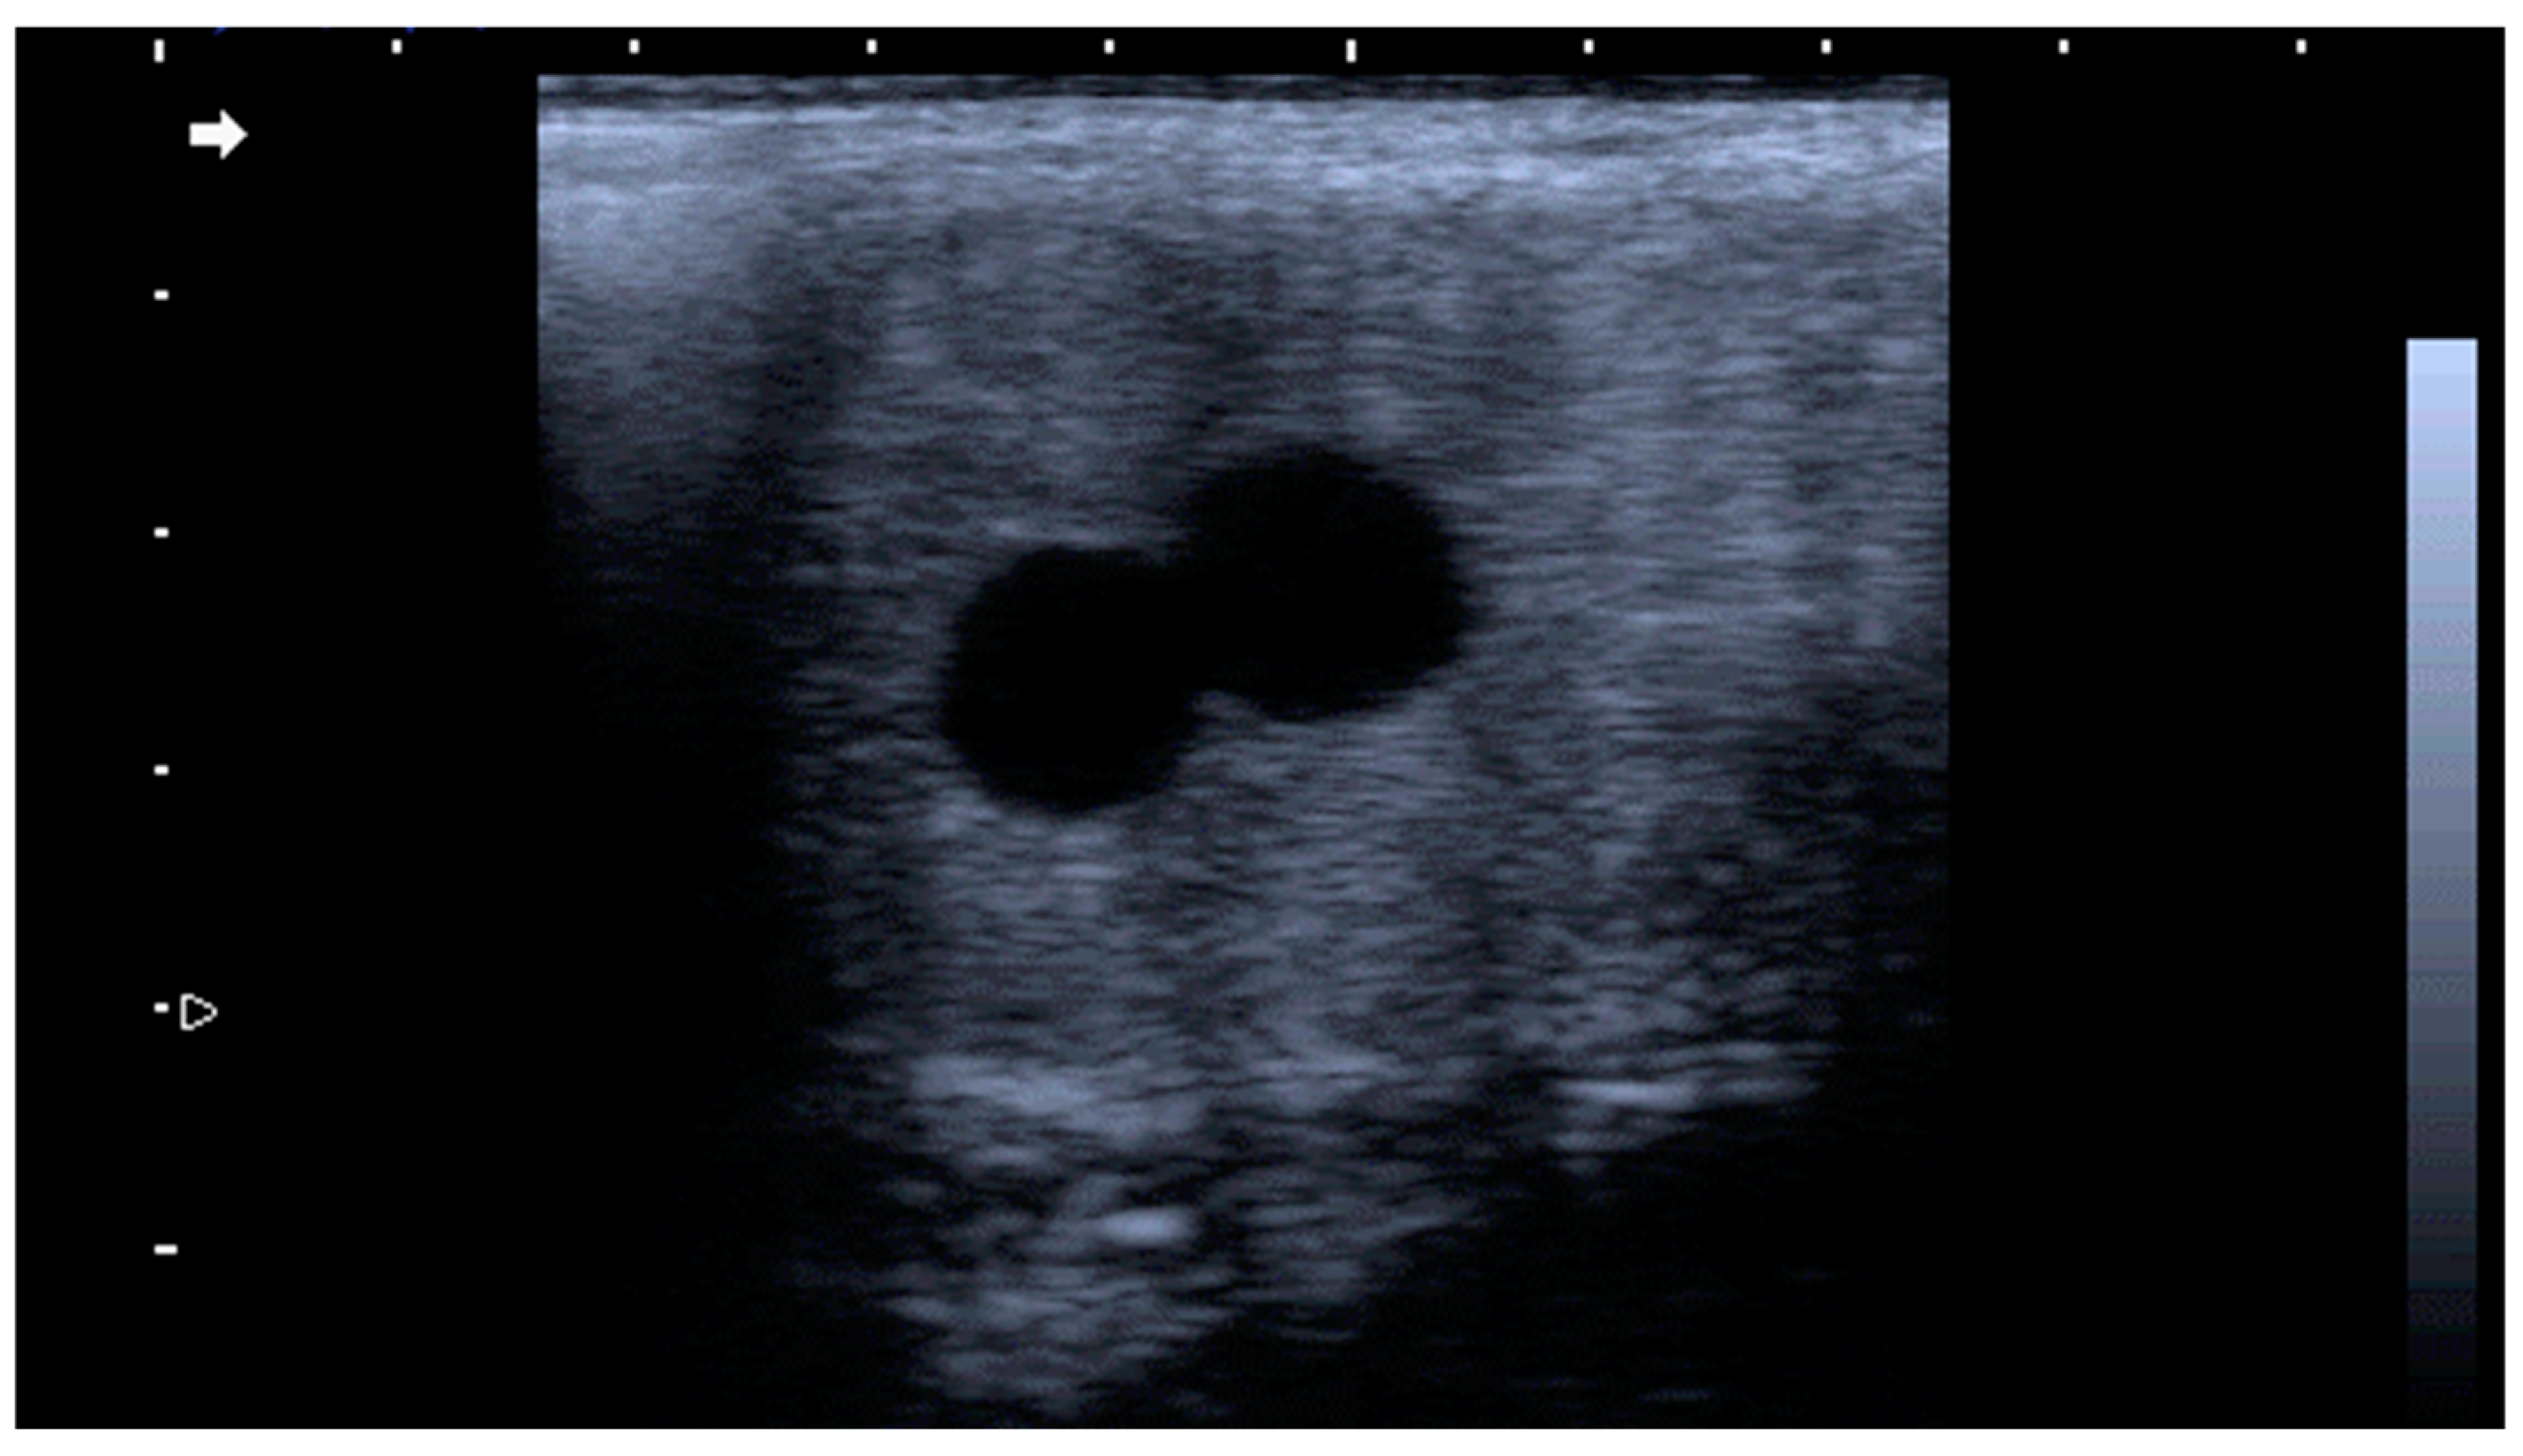

3.4. Twin Pregnancy

- Raś, A.; Raś-Noryńska, M. A retrospective study of twin pregnancy management in mares. Theriogenology 2021, 176, 183–187. [Google Scholar] [CrossRef]

- Crabtree, J.R. Management of twins in horses. Pract. 2018, 40, 66–74. [Google Scholar] [CrossRef]

- Yang, F.; Wu, S.; Zhou, J.; Yang, W.; Liu, B.; Zhang, R.; Ma, J.; Yu, J.; Ji, C.; Zeng, S. The proportion of multiple-ovulation changes among different months in Dezhou black jennies. J. Equine Vet. Sci. 2018, 66, 155–156. [Google Scholar] [CrossRef]

- Blanchard, T.; Taylor, T.; Love, C. Estrous cycle characteristics and response to estrus synchronization in mammoth asses (Equus asinus americanus). Theriogenology 1999, 52, 827–834. [Google Scholar] [CrossRef]

- Wang, Y.; Wang, T.; Zhang, Z.; Wang, C. Survival rate of donkey foals: Status quo and improvement methods. Afr. J. Biotechnol. 2021, 20, 340–348. [Google Scholar]

- Quaresma, M.; Martins, A.; Rodrigues, J.; Colaço, J.; Payan-Carreira, R. Viability analyses of an endangered donkey breed: The case of the Asinina de Miranda (Equus asinus). Anim. Prod. Sci. 2014, 55, 1184–1191. [Google Scholar] [CrossRef]

- Bonelli, F.; Nocera, I.; Conte, G.; Panzani, D.; Sgorbini, M. Relation between Apgar scoring and physical parameters in 44 newborn Amiata donkey foals at birth. Theriogenology 2020, 142, 310–314. [Google Scholar] [CrossRef] [PubMed]

- Galisteo, J.; Perez-Marin, C. Factors affecting gestation length and estrus cycle characteristics in Spanish donkey breeds reared in southern Spain. Theriogenology 2010, 74, 443–450. [Google Scholar] [CrossRef] [PubMed]

- Arangasamy, A.; Bansal, R.; Legha, R. Twin birth in a Jenny (Martina franca) with artificial insemination. Indian J. Anim. Reprod. 2006, 27, 116–117. [Google Scholar]